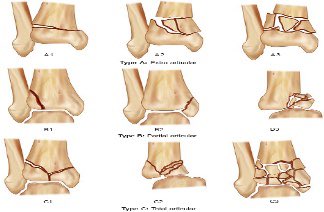

- كسر الهضبة الظنبوبية (Tibial plateau fracture).

- كسر الظنبوب عند مفصل الركبة (Proximal tibial fracture)

- كسر المحور (Tibial shaft fracture): يكون في منتصف العظمة

- كسر عند مفصل الكاحل (Distal tibial fracture)